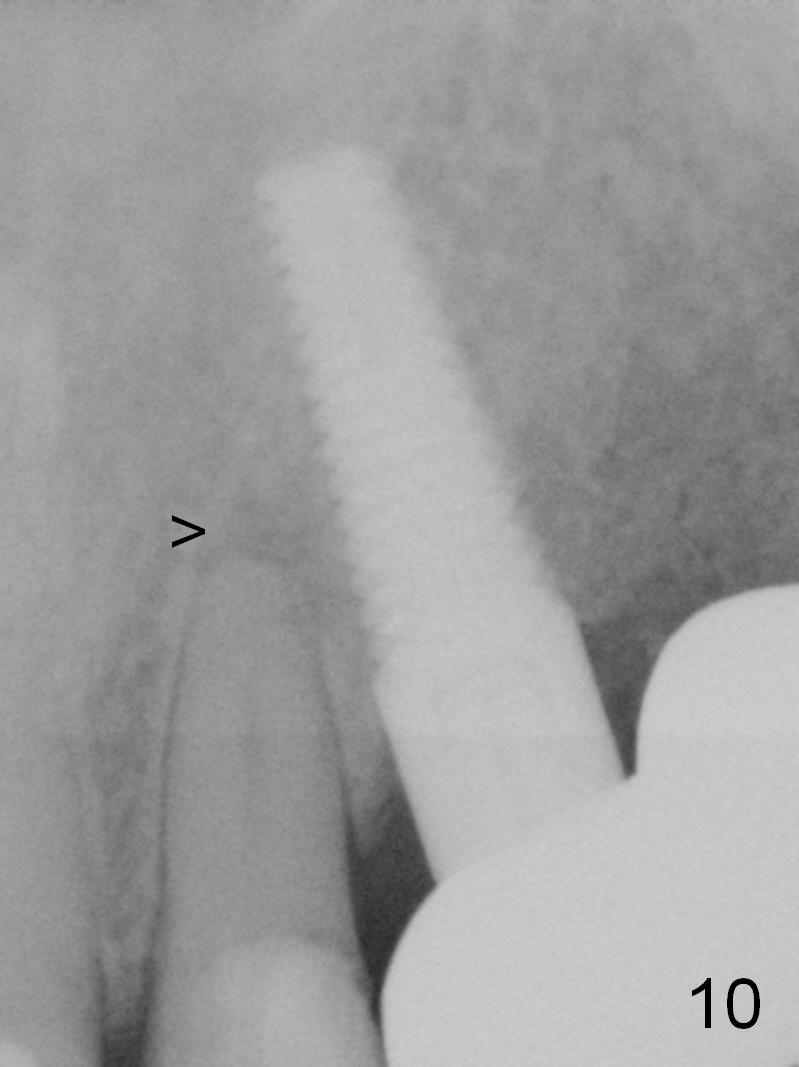

There is pain on mastication around #11, reported by the patient, 7.5 months postop (3 months post cementation). The patient refuses RCT for the tooth #10 with periapical radiolucency (Fig.10 >).